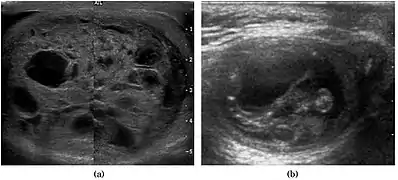

Teratoma Although teratoma is the second most common testicular tumor in children, it affects all age groups. Mature teratoma in children is often benign, but teratoma in adults, regardless of age, should be considered malignant. Teratomas are composed of all three germ cell layers, i.e. endoderm, mesoderm and ectoderm. At ultrasound, teratomas generally form well-circumscribed complex masses. Echogenic foci representing calcification, cartilage, immature bone and fibrosis are commonly seen [Fig. 5]. Cysts are also a common feature and depending on the contents of the cysts i.e. serous, mucoid or keratinous fluid, it may present as anechoic or complex structure [Fig. 6].

Fig. 6. Mature cystic teratoma. (a) Composite Image. Mature cystic teratoma in a 29-year-old man. Longitudinal sonography image of the right testis shows a multilocular cystic mass. (b) Mature cystic teratoma in a 6-year-old boy. Longitudinal sonography of the right testis shows a cystic mass containing calcification with no obvious acoustic shadow.